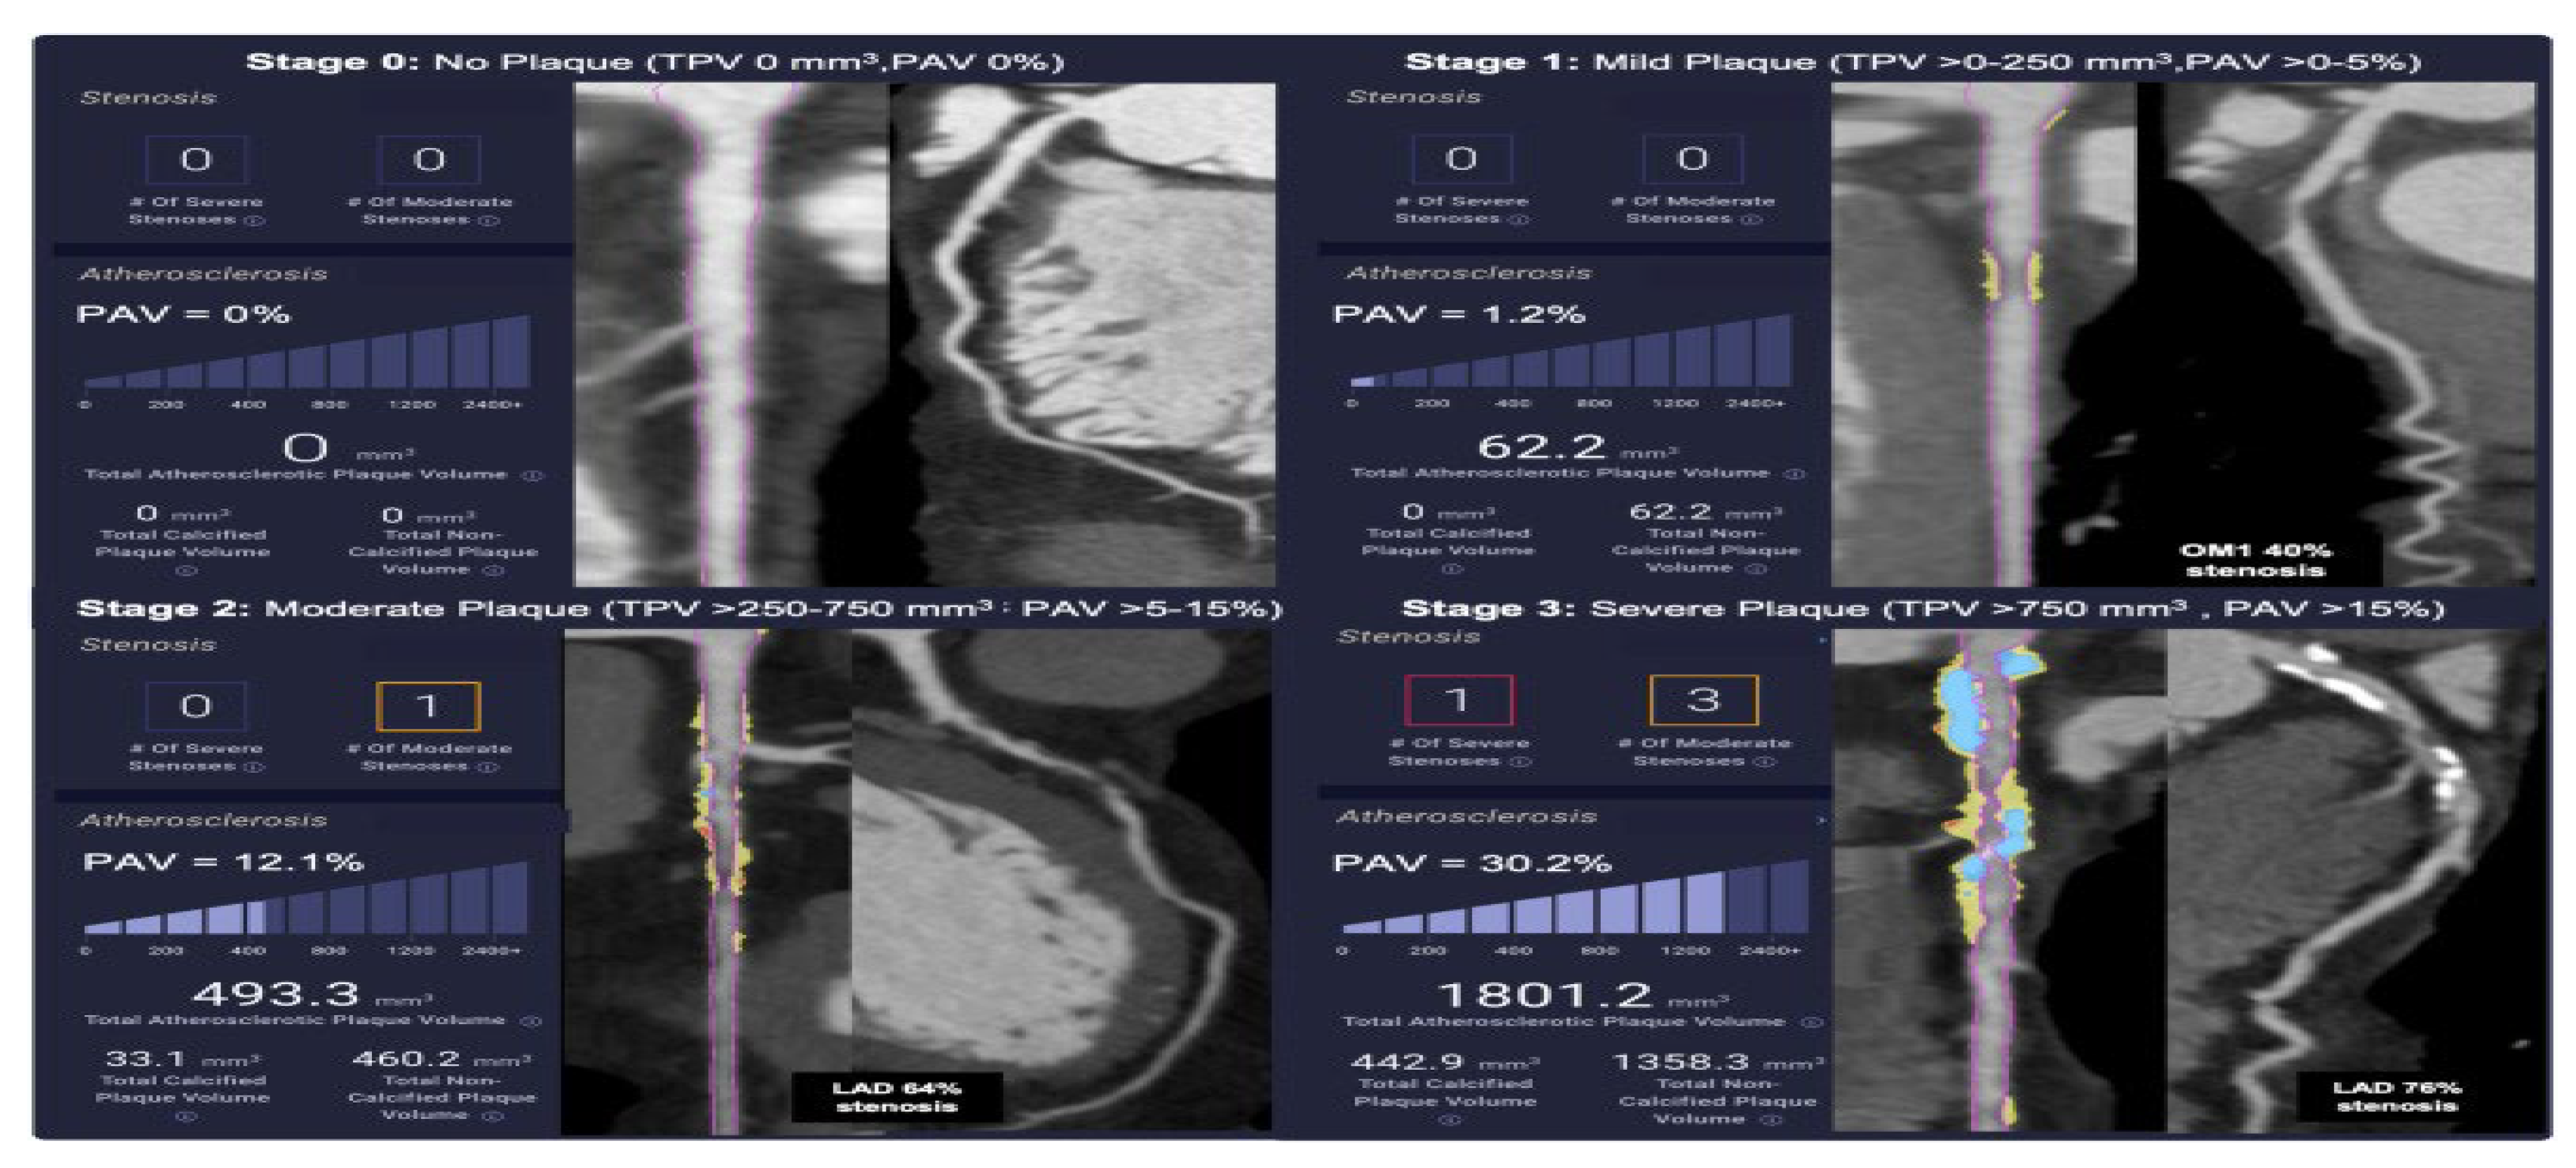

| Stages of Plaque | Total Plaque Volume (mm3) | Percent Atheroma Volume (%) | Medical Therapy |

|---|---|---|---|

| Stage 0: absence of plaque | 0, normal | 0, normal | Lifestyle modification |

| Stage 1: mild plaque | >0–250 mm3 | >0–5% | Guideline-directed; statins |

| Stage 2: moderate plaque | >250–750 mm3 | >5–15% | Moderately intensive; high-intensity statins and other agents + bempedoic acid |

| Stage 3: severe plaque | >750 mm3 | >15% | Most intensive, high-intensity statins + ezetimibe + PCSK-9i, inclisiran, etc. + bempedoic acid, etc. |